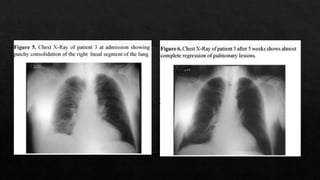

La sintomatología e imágenes difieren de

las neumonias comvencionales y pueden